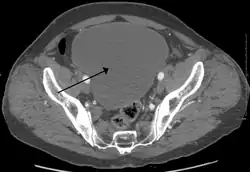

| Urinary retention with greatly enlarged bladder as seen by CT scan. | |

Analysis of urine flow may aid in establishing the type of micturition (urination) abnormality. Common findings, determined by ultrasound of the bladder, include a slow rate of flow, intermittent flow, and a large amount of urine retained in the bladder after urination. A normal test result should be 20–25 ml/s peak flow rate. A post-void residual urine greater than 50 ml is a significant amount of urine and increases the potential for recurring urinary tract infections. In adults older than 60 years, 50-100 ml of residual urine may remain after each voiding because of the decreased contractility of the detrusor muscle.[7] In chronic retention, ultrasound of the bladder may show massive increase in bladder capacity (normal capacity is 400-600 ml).